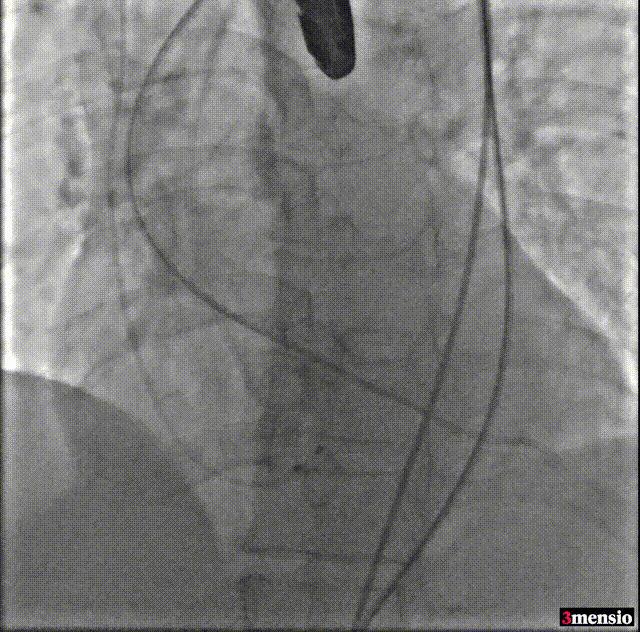

手术影像

术前冠脉造影

导丝跨瓣